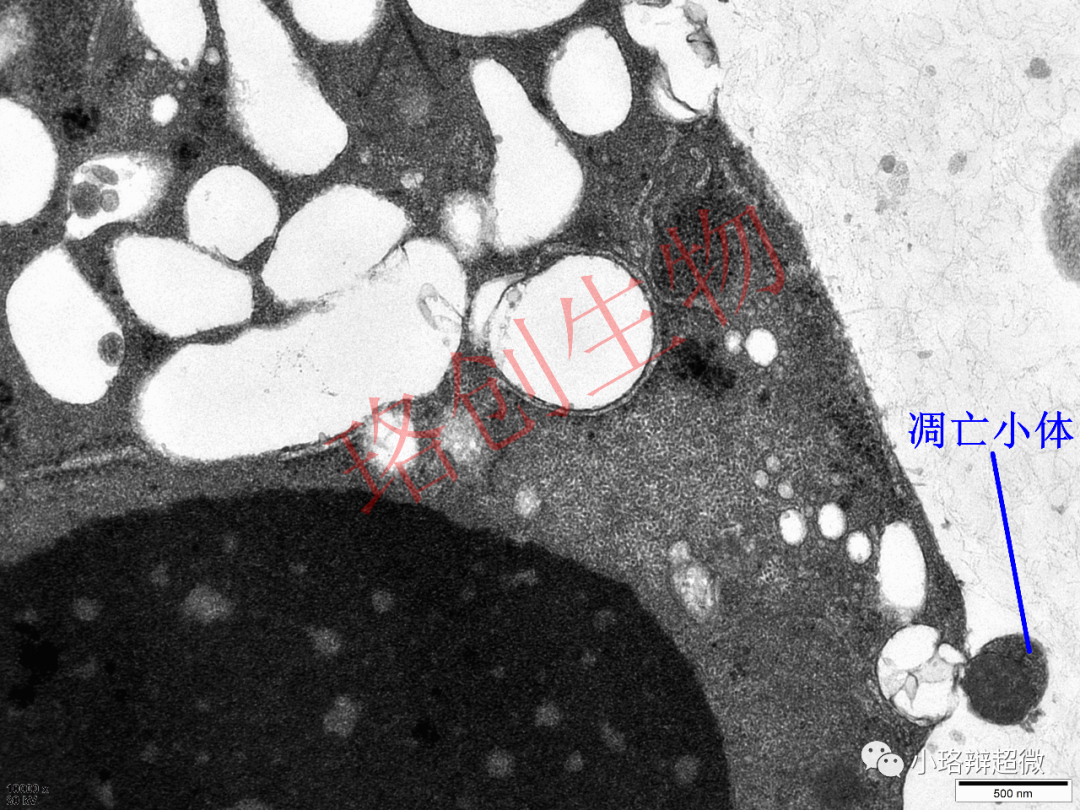

电镜下凋亡主要表现:细胞体积缩小,胞浆浓缩,结构紧密,线粒体、核糖体等聚集;染色质凝集,胞核高度固缩,并断裂成片段;凋亡小体从胞膜出芽。

凋亡小体是凋亡过程中胞膜内陷,分割胞质,形成的内含DNA或细胞器的泡状小体。可见上图凋亡小体内包裹着一个线粒体

。